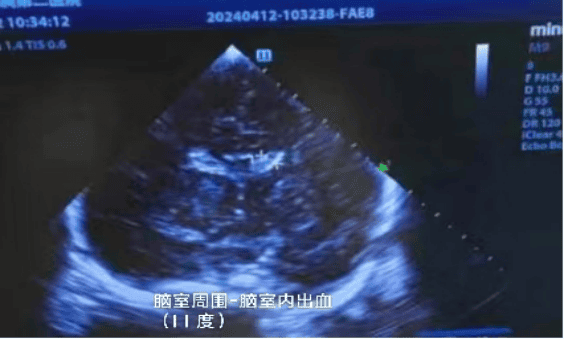

对早期诊断新生儿缺氧缺血性脑病、脑出血等获得性脑损伤具有重要价值。通过声像图对新生儿脑实质血流动力学改变、各腔隙结构、脑室以及脑实质进行详细观察,为早期诊断新生儿颅脑疾病提供影像学资料,且超声可对脑损伤的危重患儿进行床旁检查,反复动态观察,较CT、MRI等更安全价廉方便。